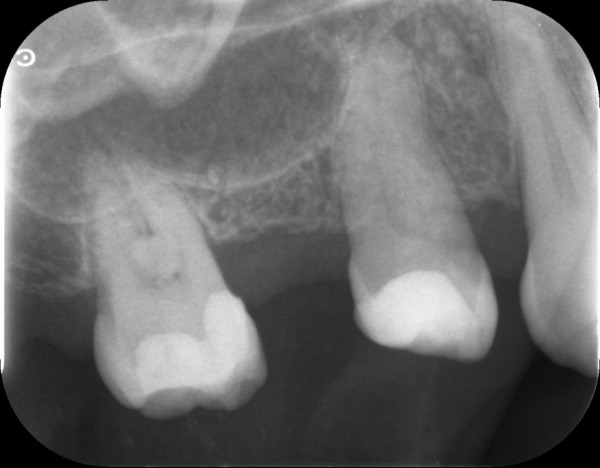

お口の中を拝見したところ、右上5・6が無く、右上4も下の歯とは噛んでいない状態でした。このことから、右側の噛み合わせが不安定なため、痛みが生じていることがわかりました。

1日目 レントゲン写真撮影後、虫歯の有無、歯周病の検査、歯石除去を行いました。治療計画のため、上下の歯型を取りました。

センター南デンタルクリニックでは、エックス線画像や口腔内写真から、患者様のお口の中で、『どういう状態なのか、なぜそうなったのか』原因を知っていただくために、歯型を取り、お口全体の話をさせていただいています。